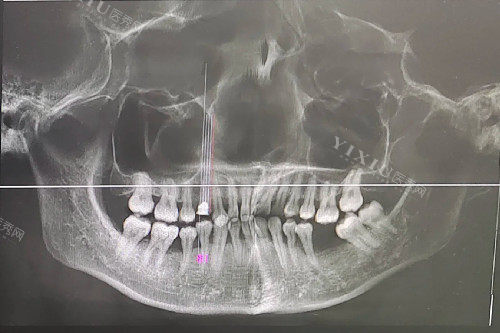

经过一段时间的治疗,牙周病得到了控制,医生说可以考虑进行牙龈填充手术了。他给我详细介绍了几种手术方法:

一种是牙龈移植术,就是从其他健康的部位取牙龈组织来覆盖萎缩的区域。医生说这种方法适用于较重的的牙龈萎缩,结果比较好,但手术相对复杂,改善时间也比较长。

还有软组织扩张技术,适用于因牙齿长期缺失导致的牙龈萎缩。通过扩张周围软组织,增加萎缩区域的软组织量,达到填充结果,术后改善较快,结果自然。

另外,还有牙龈再生术,通过植入生物材料或自体组织工程,刺激牙龈组织的再生,达到填充萎缩部位的目的,具有长期结果,但需要一定的改善时间。

我听着医生的介绍,心里很纠结。手术毕竟有风险,而且每种方法都有优缺点。我和医生反复讨论,结合我的具体情况,然后决定选择牙龈移植术。医生说我的情况比较适合这种方法,成功概率也比较高。